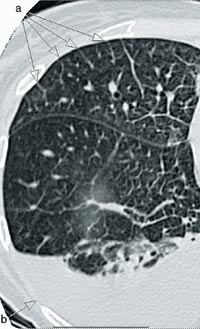

Ved autopsi var høyre ventrikkel hypertrofisk med veggtykkelse på 7 mm og høyre atrium forstørret. Det var aterosklerotiske plakk proksimalt i begge lungearterier, med mindre trombotiske påleiringer perifert uten tegn til okklusjon. Mikroskopisk undersøkelse viste tydelig veggfortykkelse av små kar, og tynnveggede vener var vanskelig å identifisere. Ved elastinfarging fant vi betydelig intimafibrose, til dels med obliterasjon, i mange små lungevener (fig 2). Pleksiforme lesjoner som er typiske ved pulmonal arteriell hypertensjon, var ikke påvisbare.

Det er enighet om at de primære patologiske forandringene foreligger på den venøse siden i lungene, selv om mediahypertrofi i arterioler også forekommer. Mikroskopisk kan forandringene på venesiden lett overses ved at fortykkede vener oppfattes som små arterier. Bruk av elastinfarging vil avklare en slik usikkerhet ved å gjøre synlig at små vener mangler den indre elastiske membran. Det histologiske bildet med obliterering og okklusjon av mindre pulmonale vener oppfattes indusert av karskade. Ulike mekanismer for traume mot karveggen er foreslått, slik som infeksjon, genetisk disposisjon, eksposisjon av toksiske substanser, trombotiske forstyrrelser og autoimmun sykdom. Vår pasient var røntgenbestrålt mer enn fem år før det aktuelle som ledd i behandlingen av underlivskreft, og det er beskrevet assosiasjoner mellom bestråling og venookklusiv sykdom (5), riktignok ved lymfom og bestråling av lungefelt. En vel så sannsynlig sammenheng kan knyttes til pasientens sklerodermi og CREST-syndrom, idet venookklusiv sykdom har vært beskrevet ved ulike autoimmune sykdommer (6, 7). En mulig mekanisme er autoimmun destruksjon av pulmonale venyler, primært eller sekundært til en viral infeksjon, med påfølgende trombose og fibrose. Da biopsifunnene ikke er entydige med hensyn til inflammatoriske forandringer, er det naturlig å tenke seg flere årsaker/agenser som alle deler de histologiske særtrekk med obliterasjon og okklusjon av de små pulmonale vener.